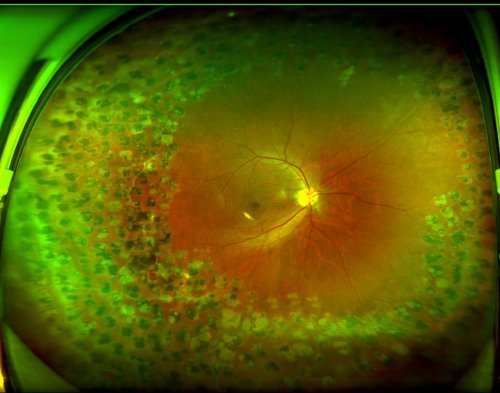

“因双眼在外院做过多次视网膜激光光凝术,视网膜周边形成了多量点状激光瘢痕。这些瘢痕与正常视网膜粘连紧密,大大增加了手术的复杂性和风险。对主刀医生的技术要求高——需要更丰富的经验、更精湛的显微手术技术,以及应对复杂组织变化的能力。”

图:张先生右眼眼底

2026年1月20日,赵铁英院长为张先生顺利实施了“右眼微创玻璃体视网膜病变手术+黄斑前膜、内界膜剥离术+气体填充术”。